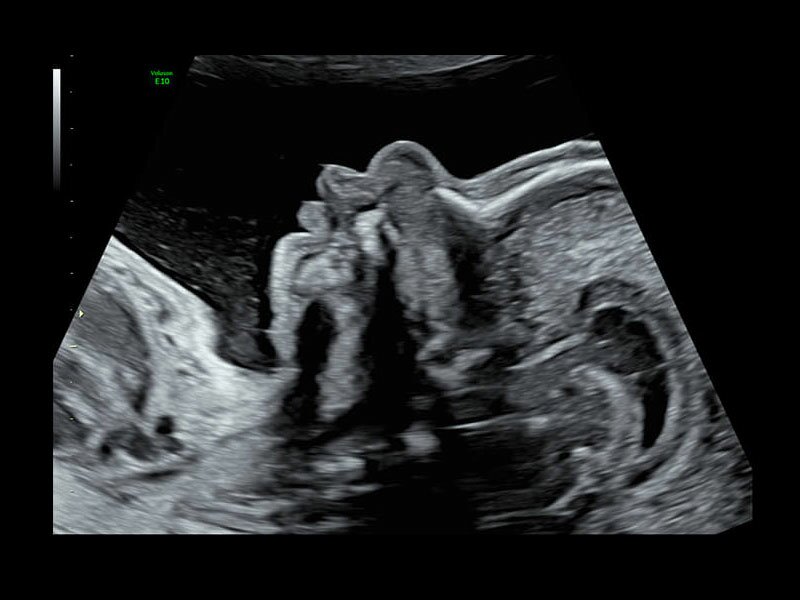

Клинические изображения

Объемное сканирование Voluson — 3D/4D вашей мечты

Объемное УЗИ на Voluson E10 — это не просто потрясающе красивая картинка, это ценный инструмент получения дополнительной информации при обследовании женщин.

Voluson E10 поддерживает инновационные технологии формирования изображений — HDlive Silhouette и HDlive Flow, которые позволяют увидеть мельчайшие детали. Алгоритм SonoRenderlive упрощает рабочий процесс и дает возможность реконструировать изображение поверхностей, определяя область перехода между тканью и жидкостью.

Инновационная технология визуализации HDlive обеспечивает получение реалистических изображений за счет эффекта объемного зрения, повышая достоверность клинической оценки. Теперь режим HDlive дополняют две новые функции:

• Технология HDlive Silhouette — задает разный уровень прозрачности, помогая выявлять контуры внутренних структур и точнее оценивать состояние плода в первом триместре.